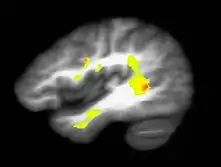

Brain of a cannabis user

No clear evidence of these links have been provided.